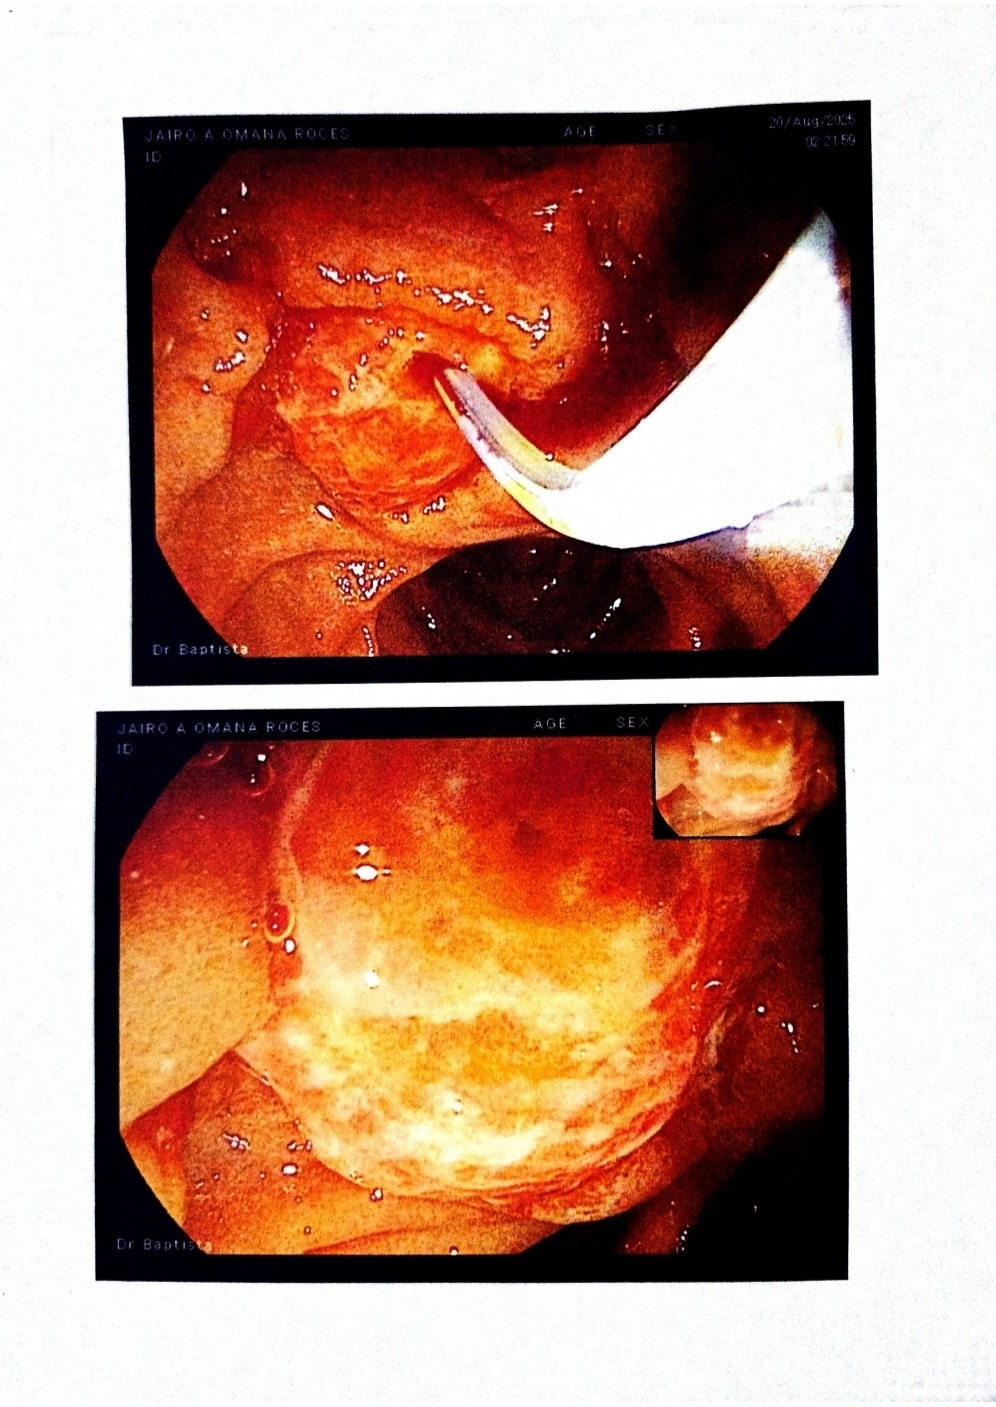

El estar lejos, ha sido bien difícil para mí, porque me ha tocado pasar todo este proceso lejos de ellos. Sin embargo, el estar aquí, me ha permitido apoyarlos económicamente, con; exámenes, consultas, medicamentos, dieta alimenticia estricta y otros procedimientos médicos menos invasivos y un poco menos costosos que han sido de vital importancia y que también necesitaba de urgencia para este momento (porque estaba presentando "ictericia obstructiva y dilatación de las vías biliares a causa del tumor que fue descubiertos en exámenes posteriores", en otras palabras, el tumor le estaba tapando el conducto por donde se desplaza el flujo biliar en el organismo, situación bastante delicada, porque puede llevar a un colapso general del organismo).. Estuvo presentando síntomas, como; color amarillento en piel y ojos, dolor de estómago, heces de color claro y picazón generalizada. Por ello se le realizó una colangiopancreatografía retrógrada endoscópica o CPRE, procedimiento médico que combina endoscopia y radiografías, donde se efectúo una esfinterotomía y drenaje biliar con colocación de un stent plástico en el conducto, atacando los síntomas mencionados, permitiendo el flujo correcto por el conducto y así evitar consecuencias más graves. Así mismo, le permitió al especialista dar con el diagnóstico exacto ADC DE PAPILA DE VATER uT2N0M0.

-Pág 1 y 2, Presupuesto del Hospital de Clínicas Caracas de fecha 29/08/2025, válido por 5 días, sin impuestos incluidos, expresado en la moneda nacional y en dólares.-Pág 3 Informe médico del Gastroenterólogo con los hallazgos obtenidos por la realización de la Colangiopancreatografía retrógrada endoscópica. Incluyendo un ultrasonido endoscópico y toma de muestra para la biopsia.-Pág 4 y 5 imágenes de la masa tumoral en el conducto biliar.-Pág 6, resultados de la biopsia.-Pág 7 y 8, Informe médico del cirujano oncologo.-Pág 9 y 10, TAC Abdomen y pelvis con doble contraste.-Pág 11, Resonancia magnética de abdomen con efecto colangiografía.-Pág 12 y 13, Estudio con transductor convex multifactorial de alta definición.

Being away has been very difficult for me because I've had to go through this entire process away from them. However, being here has allowed me to support them financially, with tests, consultations, medications, a strict diet, and other less invasive and somewhat less expensive medical procedures that have been vitally important and that he also urgently needed at this time (because he was presenting with "obstructive jaundice and dilation of the bile ducts due to the tumor that was discovered in subsequent tests." In other words, the tumor was blocking the duct through which bile flows in the body, a very delicate situation because it can lead to a general collapse of the body). He was experiencing symptoms such as yellowing of the skin and eyes, stomach pain, light-colored stools, and generalized itching. Therefore, the patient underwent endoscopic retrograde cholangiopancreatography (ERCP), a medical procedure that combines endoscopy and X-rays. This procedure involved sphincterotomy and biliary drainage with placement of a plastic stent in the duct. This procedure addressed the aforementioned symptoms, allowing proper flow through the duct, and thus avoiding more serious consequences. This procedure also allowed the specialist to make the exact diagnosis: ADC of papilla of Vater uT2N0M0.

-Pages 1 and 2, Hospital de Clínicas Caracas budget dated August 29, 2025, valid for 5 days, excluding taxes, expressed in local currency and dollars.-Page 3, Gastroenterologist's medical report with the findings obtained from the endoscopic retrograde cholangiopancreatography. Including an endoscopic ultrasound and biopsy sample collection. - Pages 4 and 5, images of the tumor mass in the bile duct. - Pages 6, biopsy results. - Pages 7 and 8, medical report from the oncological surgeon. - Pages 9 and 10, CT scan of the abdomen and pelvis with double contrast. - Pages 11, MRI of the abdomen with cholangiography effect. - Pages 12 and 13, High-definition multifactorial convex transducer study.